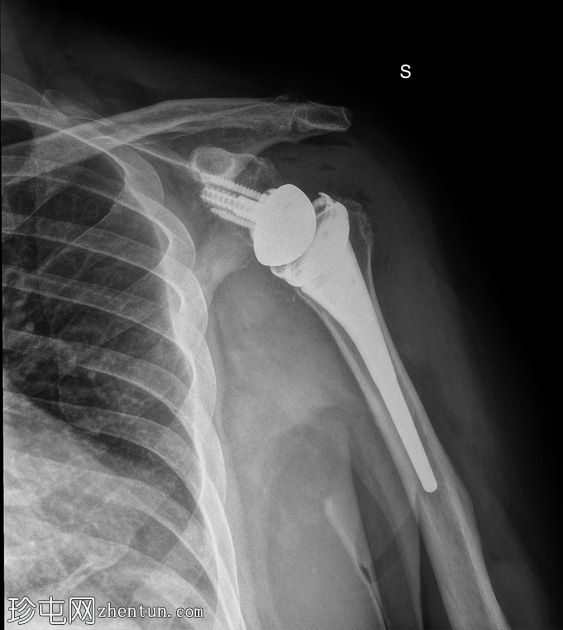

正面

胸部侧面图:肱骨假体前脱位,盂球固定到位。和纵隔正常。无胸腔积液。

全肩关节置换术后肱骨假体前脱位,伴假体分离。